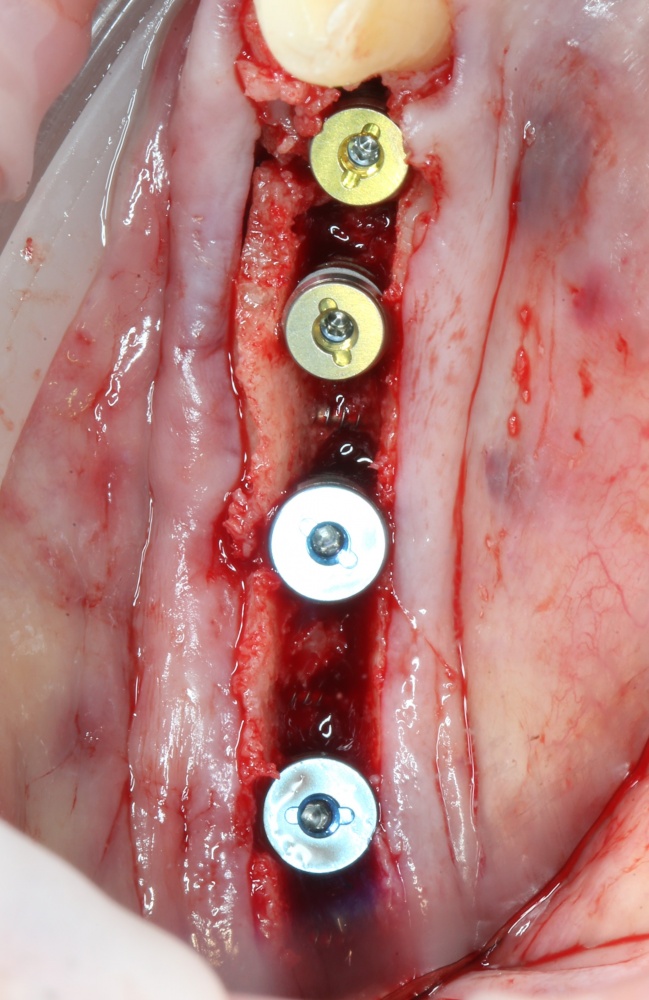

Во-вторых, мы, фактически, сразу создаём идеальные условия для регенерации костной ткани — наш костный дефект со всех сторон окружён раневой поверхностью, а это значит, что миграция клеток и рост будут идти со всех сторон (см. «Предел роста»). Это чем-то похоже на синуслифтинг, неудачи в котором крайне редки:

В-третьих, достаточно большая раневая поверхность «привлекает» большее количество макрофагов, следовательно, мы имеем больше БКМ, факторов роста, управляющих регенерацией кости. Уточню — без добавления аутокостной стружки или чего-то там искусственного:

В-четвертых, мы можем восполнять как вертикальную